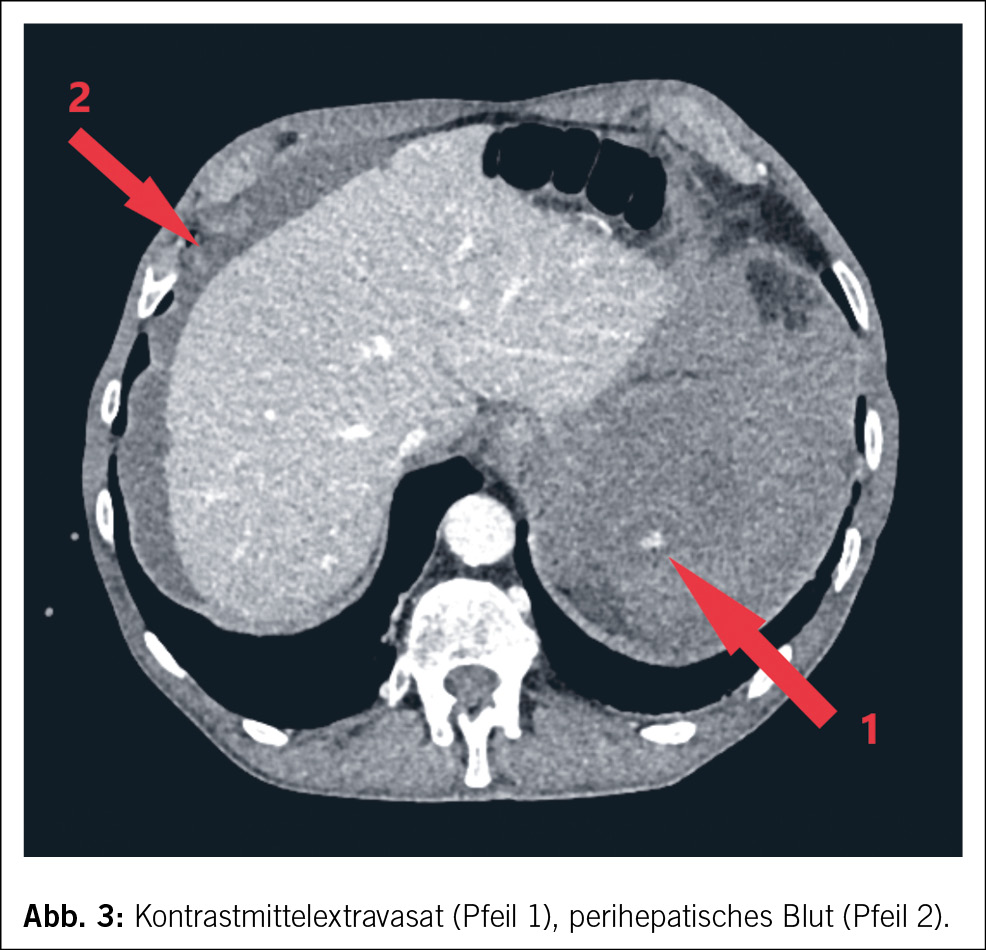

In der Computertomographie (Abb. 1) konnte intraabdominal viel freies Blut dokumentiert werden. Ätiologisch zeigte sich eine Milzblutung mit grossem subkapsulärem Hämatom und eine aktive Blutung der Milz in die Bauchhöhle (Abb. 2 und 3), entsprechend einer Verletzung Grad IV nach der American Association for the Surgery of Trauma (AAST) grading scale for splenic lacerations (7). Diese Einteilung richtet sich nach der Grösse des subkapsulären Hämatoms, dem Vorhandensein eines Kapselrisses, dem Ausmass der Organlazeration und dem Vorhandensein einer aktiven Blutung.